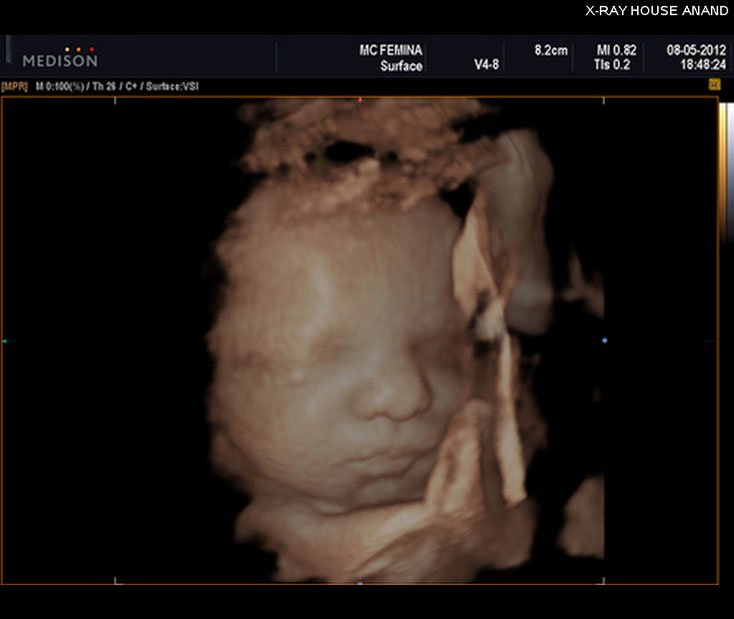

4D Foetal Face

4D Sonography -Foetal Face